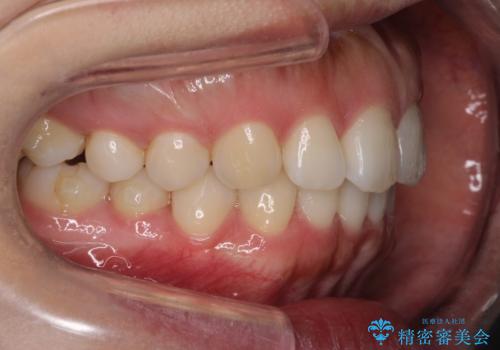

- 前歯の歯並びの改善を希望され来院された患者様です。

初診時の歯並びの状態としては、下顎前歯に及ぶの中等度のがたつき(叢生)があり、前歯が深く噛みこんでいる状態でした。

抜歯は行わず歯列弓の拡大やディスキング(歯と歯の間の隙間を作る処置)を行い叢生を改善しました。

見た目、嚙み合わせ及び、治療期間や施術内容に大変ご満足いただきました。